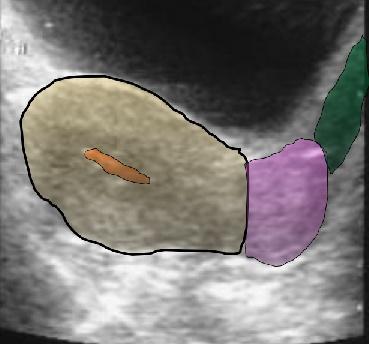

Absceso Tuboovárico (TOA)

Es una inflamación donde

la acumulación de material purulento se extiende más allá de los confines de las trompas.

Esta infección se ha dispersado a los ovarios y a la superficie peritoneal.

El TOA lo podemos observar unilateral o bilateral.

Es una lesión compleja que contiene fluido y material purulento, usualmente se observa la lesión en el CDS.

Hallazgos Sonográficos:

Usualmente observamos

una masa compleja con septaciones, márgenes irregulares y ecos internos; usualmente en el CDS.

Fluid- Fluid level

El ovario es difícil de reconocer o diferenciarlos de la masa.

Esta masa distorsiona la anatomía pélvica.